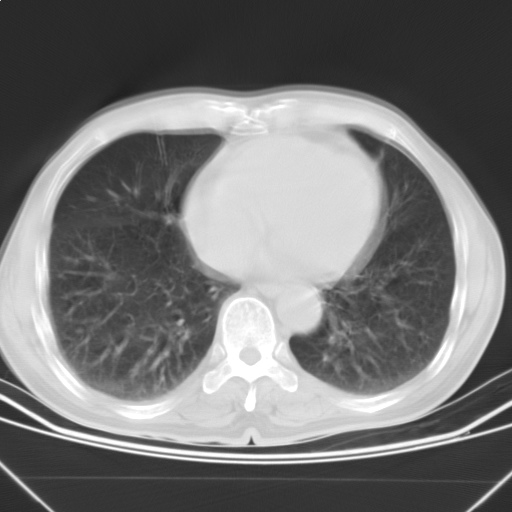

以下是引用随光逐影在2009-5-1 13:53:00的发言:[br]考虑为:1)两肺血行播散型肺结核;2)右肺下叶炎症感染。3)右侧胸膜增厚。